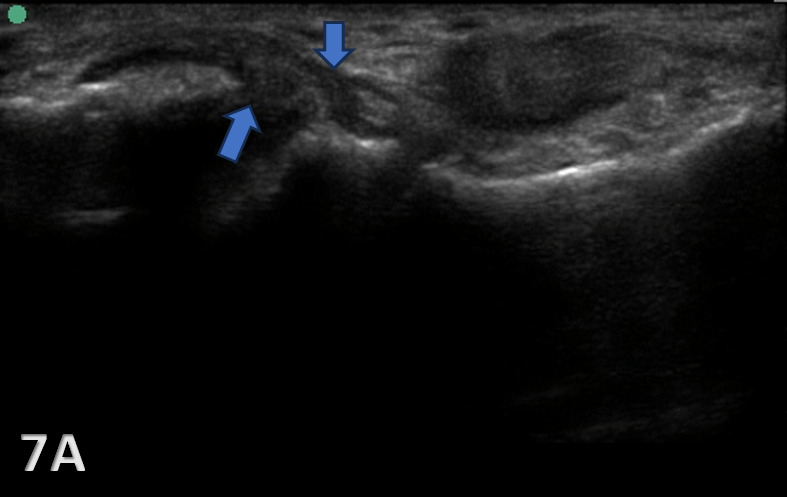

PARTIAL TEAR OF CFL

Figure 7A: The CFL will be hypoechoic and thickened or swollen in case of a partial tear and sprain (blue arrows). Partial tears might show anechoic defects and undulated or irregular ligament fibers.